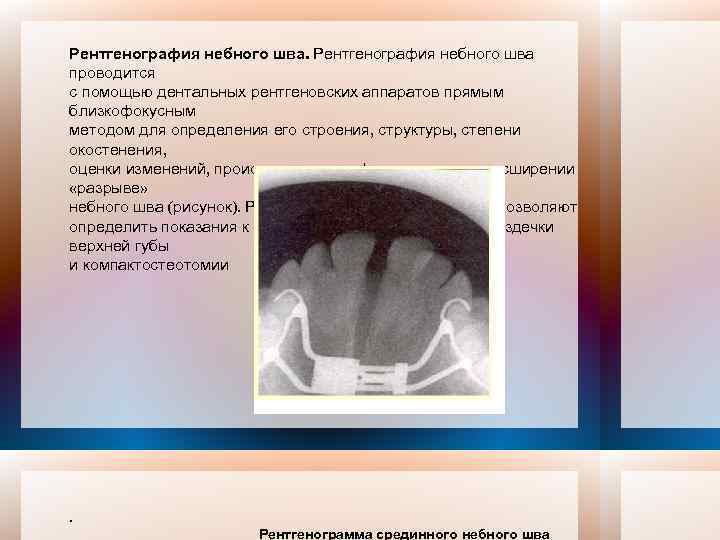

Рентгенография небного шва: Медицинские исследования и диагностика

Раздел: Фотопутеводитель